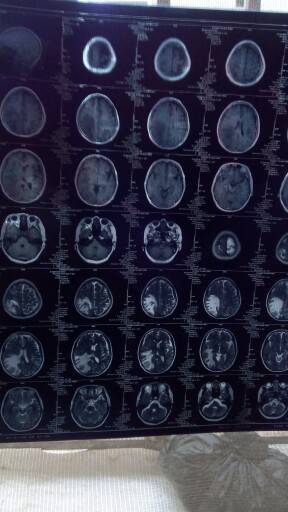

妈妈肺部和脑部肿瘤消失了